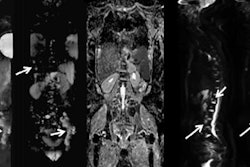

Dr. Esin Gezmis.The most common metastatic sites of lung cancer are bone, brain, liver, and adrenal glands, but it can spread to nearly any organ, including the heart. Lung cancer can spread to the heart and pericardium, and metastatic involvement of the heart is approximately 40 times more prevalent than primary cardiac tumors and is generally associated with a poor prognosis, Gezmis explained. Primary lung cancer represents 36% to 39% of cardiac metastases.

"Identifying the tumor, node, and metastasis (TNM) stage of the lung cancer correctly is very important, because the determination of the appropriate treatment is mainly based on that," she stated. "The evidence of intra- and extrathoracic metastasis changes the management of these patients, and can eliminate the surgery option, which generally results in a poorer outcome."

The 69-year-old woman was admitted to hospital with chest pain, dysarthria, and left-sided hemiparesis. Her head CT and head MR scans revealed no evidence of acute infarct, intracranial mass, or hemorrhage, but the chest x-ray showed an incidental mass in the lower zone of the right lung. A contrast-enhanced thoracic CT scan demonstrated a spiculated mass (31 x 29 x 24 mm in size) with a low attenuation center. There was also a 10-mm right hilar node, but no evidence of satellite lung lesions or pleural thickening. The appearances were thought to be consistent with primary lung malignancy, the radiological staging of which was T1b, N1, M0, she added.